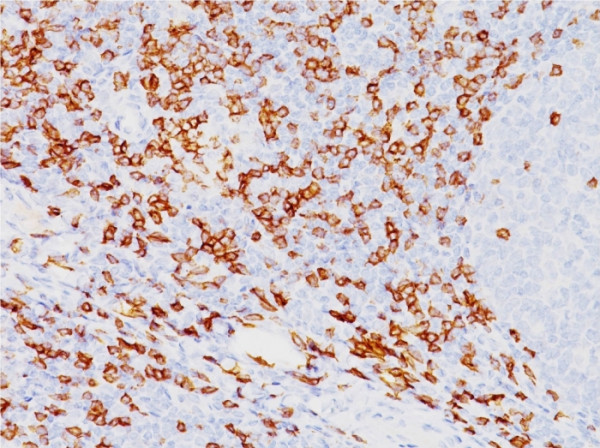

Product information "Anti-CD8a (Cytotoxic-&Suppressor T-Cell Marker), clone SPM548"

Formulation: Purified Ab WITHOUT BSA and Azide at 1.0mg/ml. Cellular Localization: Cell membrane, Secreted. Positive Control: HuT78 or hPBL cells. Human lymph node or tonsil. Chromosome Location: 2p11.2. Protein Function: Integral membrane glycoprotein that plays an essential role in the immune response and serves multiple functions in responses against both external and internal offenses. In T-cells, functions primarily as a coreceptor for MHC class I molecule:peptide complex. The antigens presented by class I peptides are derived from cytosolic proteins while class II derived from extracellular proteins. Interacts simultaneously with the T-cell receptor (TCR) and the MHC class I proteins presented by antigen presenting cells (APCs). In turn, recruits the Src kinase LCK to the vicinity of the TCR-CD3 complex. LCK then initiates different intracellular signaling pathways by phosphorylating various substrates ultimately leading to lymphokine production, motility, adhesion and activation of cytotoxic T-lymphocytes (CTLs). This mechanism enables CTLs to recognize and eliminate infected cells and tumor cells. In NK-cells, the presence of CD8A homodimers at the cell surface provides a survival mechanism allowing conjugation and lysis of multiple target cells. CD8A homodimer molecules also promote the survival and differentiation of activated lymphocytes into memory CD8 T-cells [The Uniprot Consortium]

| Application: | FC, IF, IHC |